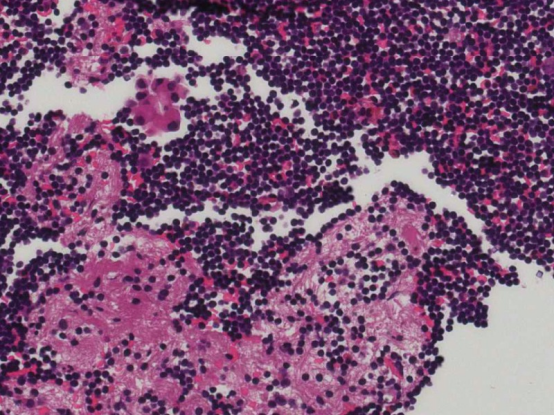

正是这关键的一步,让“隐形”的肿瘤细胞现了原形!在细胞蜡块切片下,病理医师清晰观察到肿瘤细胞的异型性、排列方式等特征,结合免疫组化结果,最终明确该胸腔积液来源于恶性肿瘤转移,为临床精准分型、开展后续治疗赢得了宝贵时间。

100×,查见异型腺体